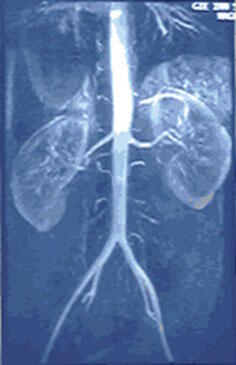

Des maladies des reins sont fréquentes chez les patients diabétiques. Quatorze anciens combattants avec un diabète de type II avancé ont eu leur alimentation supplémentée avec un isolat de protéine de soja ou avec de la caséine de lait pendant deux périodes de traitement de huit semaines dans le cadre d'une étude qui a duré sept mois. Les quantités de protéines données à chaque patient ont été calculées en fonction de leur poids. Des échantillons d'urine et de sang ont été collectés au début et à la fin de l'étude.